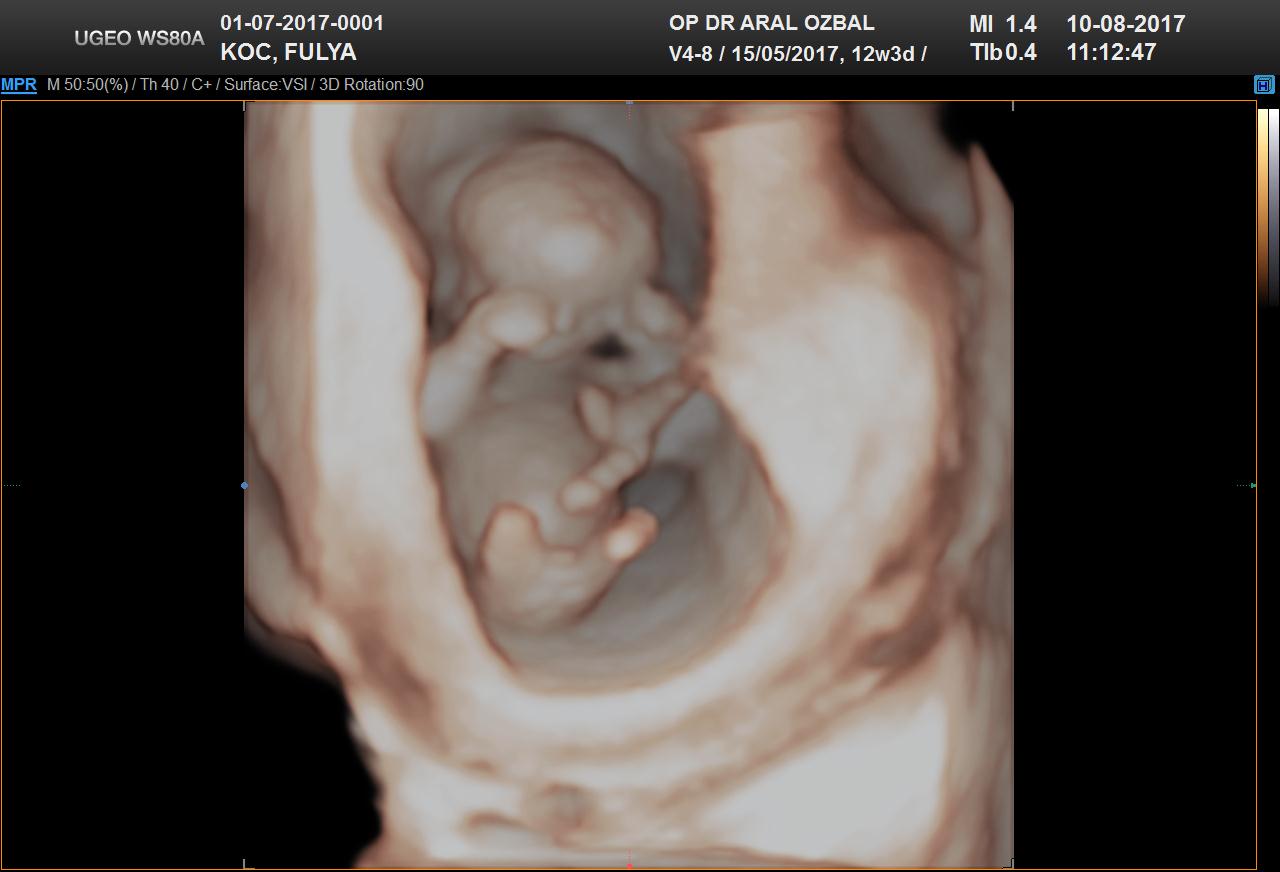

B Baharr@86 Forum Okuru 14 Ağustos 2017 #27 Benimkinede bakabilirmisiniz. 12+3 haftalık Ekli dosyalar 20170810111903_967.jpg 94,5 KB · Görüntüleme: 946 20170810111903_390.jpg 69,9 KB · Görüntüleme: 927

Uzman SühaN Administrator 14 Ağustos 2017 #28 Merhaba nub teorisine göre bebeğin poziyonu yan olmalı . Uygun görsele sahip değilsiniz bu yüzden değerlendirme yapamıyoruz.

Merhaba nub teorisine göre bebeğin poziyonu yan olmalı . Uygun görsele sahip değilsiniz bu yüzden değerlendirme yapamıyoruz.